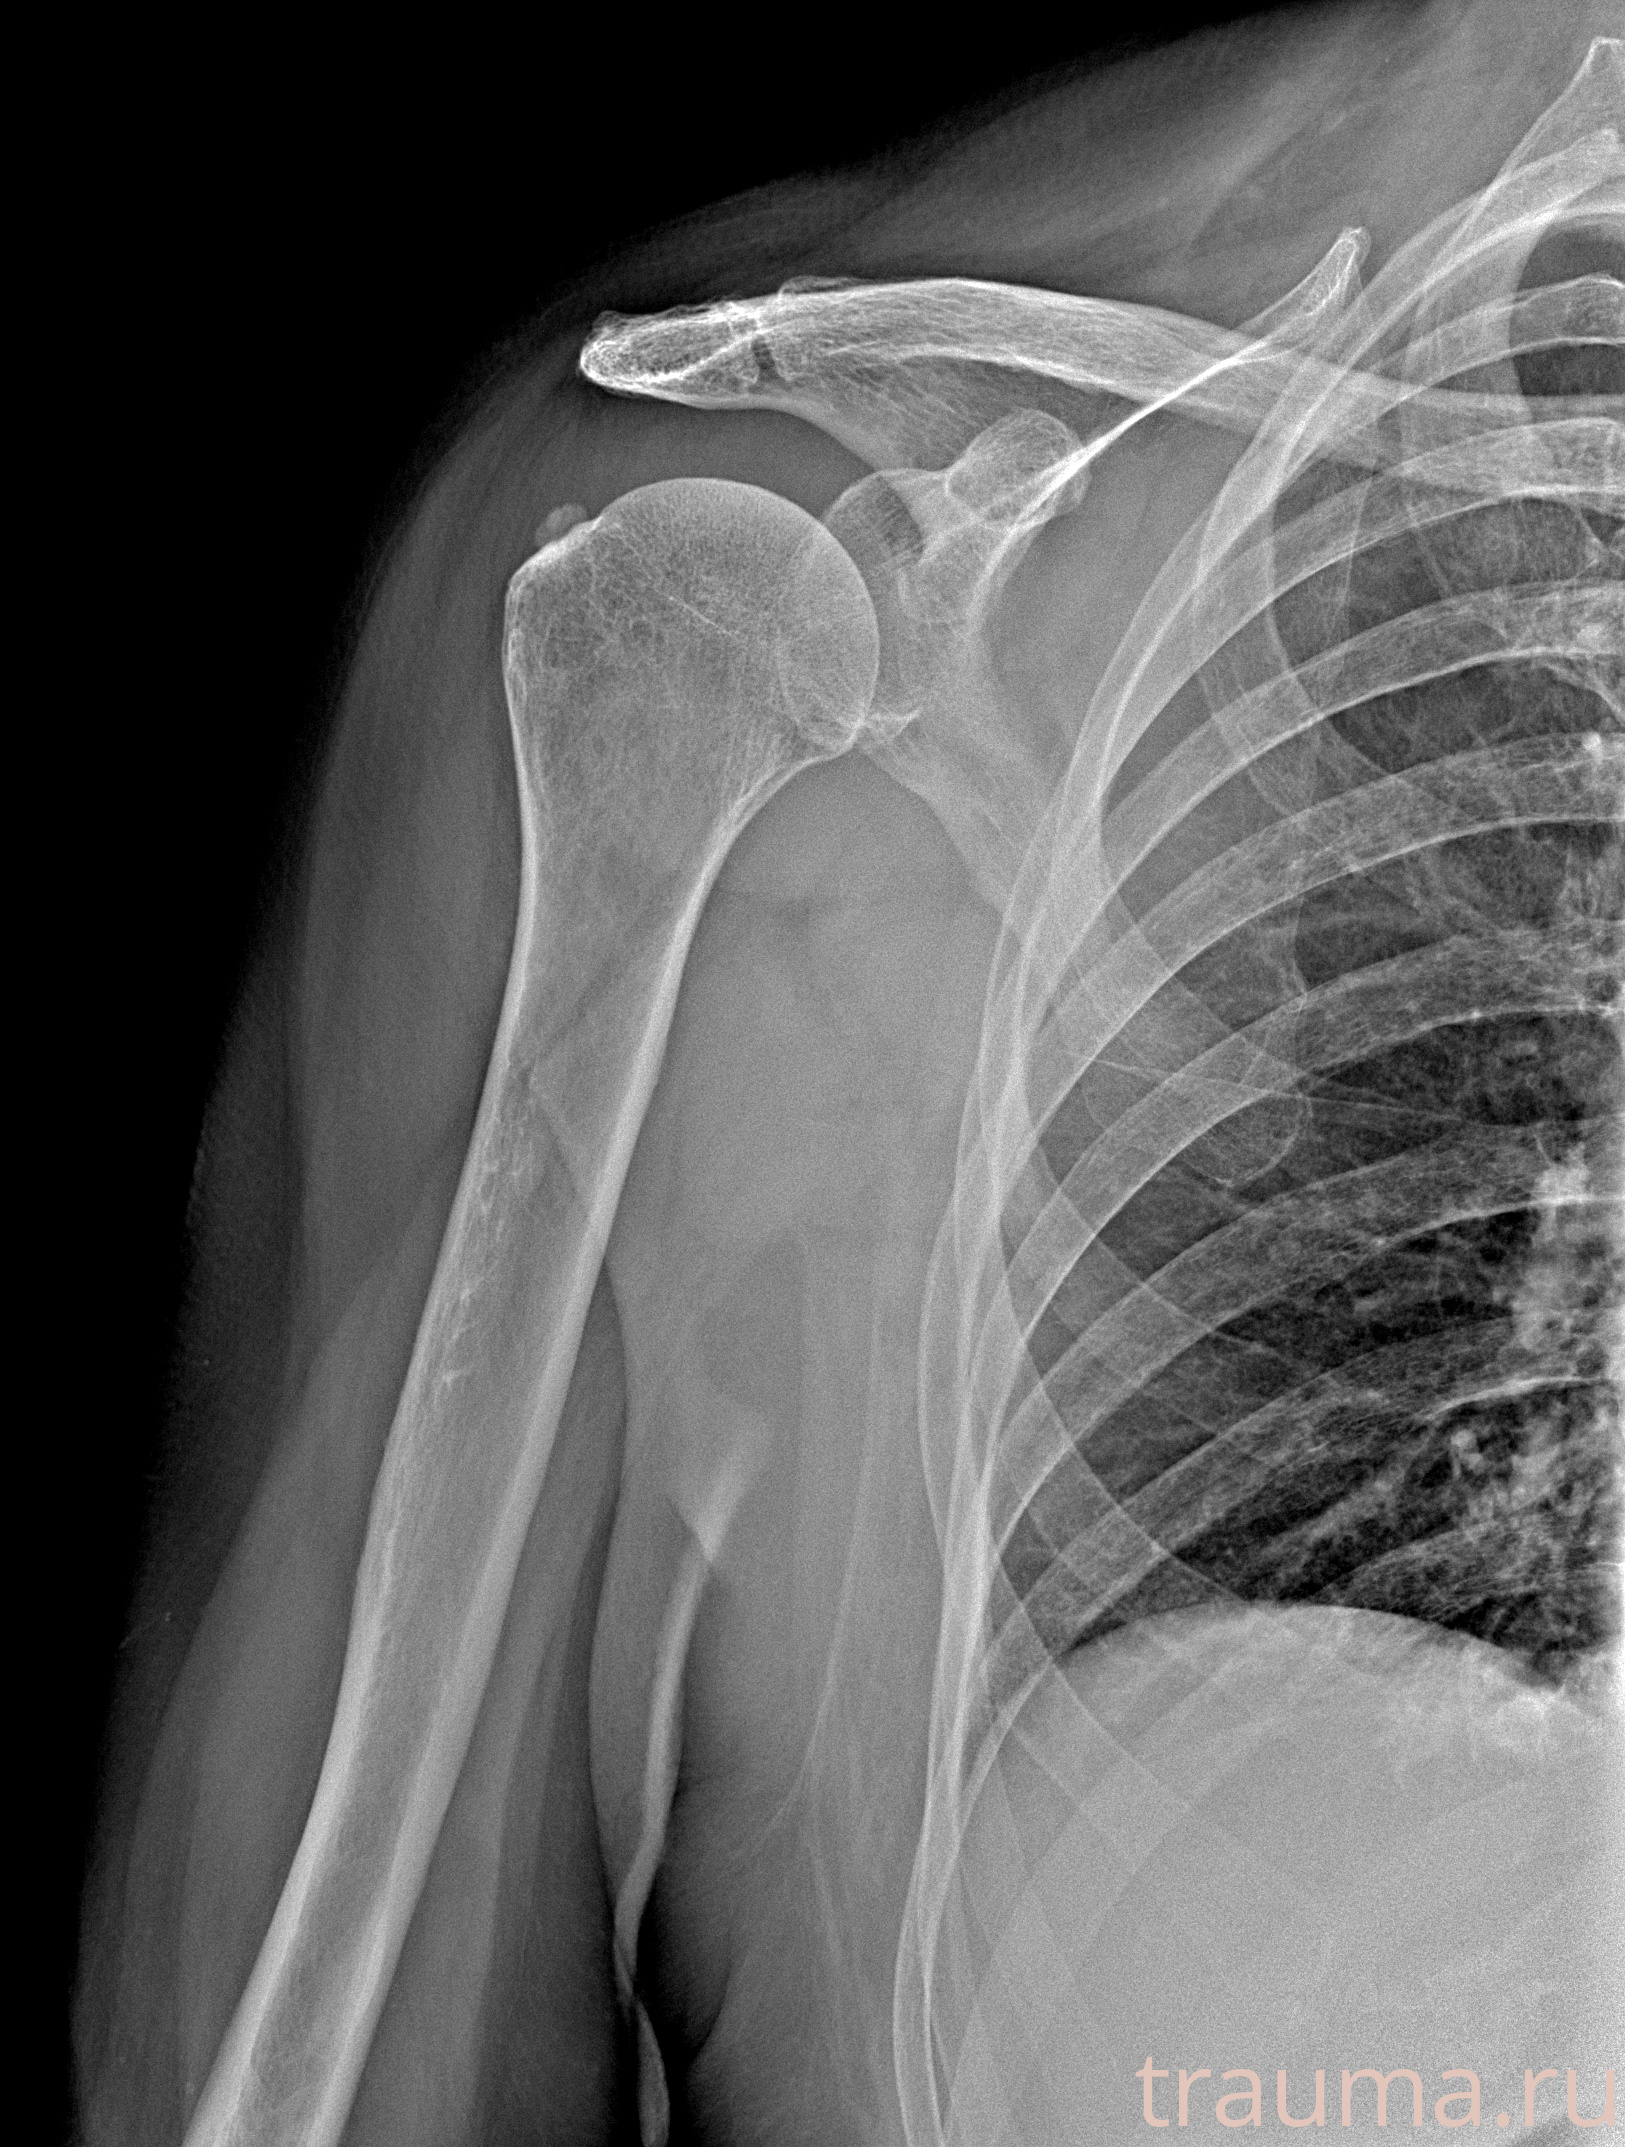

Рентгенограммы

Рентген на дому: по вашему адресу приезжает врач-рентгенолог, травматолог-ортопед с мобильным рентгеновским аппаратом, проводит диагностику травмы или заболевания, делает необходимые рентгенограммы, дает рекомендации по дальнейшему лечению. Получить качественные снимки в домашних условиях возможно благодаря уникальной методике, разработанной МосРентген Центром для института  Склифосовского